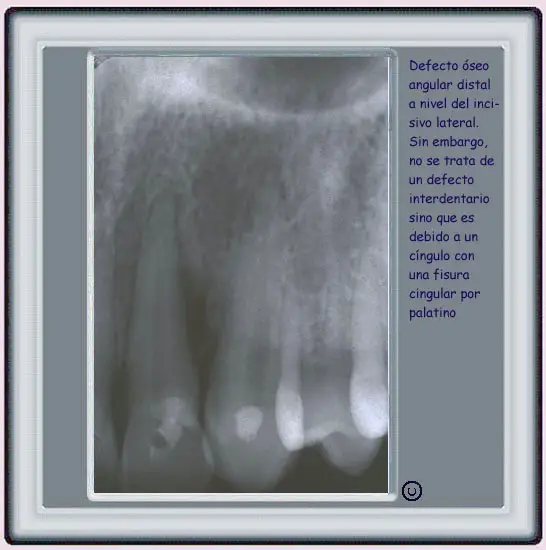

image237